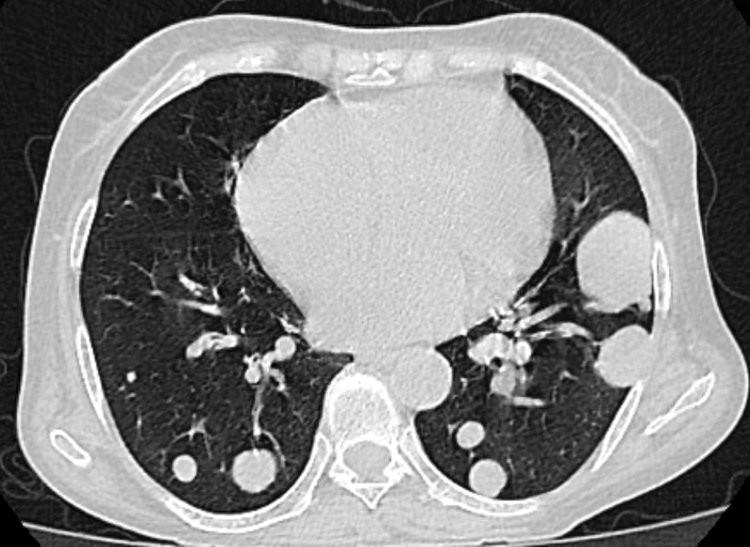

首先要搞懂結節到底什麼? 其實,結節並不是病。它是影像學檢查中的一個描述性名詞,指的是病竈的大小而非性質。在影像學上表現爲球狀或近似球狀的凸起物,從觸覺上來說就是個小腫塊,在肺病、甲狀腺、肝臟以及乳腺等多個部位均可出現。

• 肺結節

肺結節的發生與多種因素相關,如先天性因素、病毒/細菌/真菌感染、吸菸、石棉等,也可能是外傷或是疾病留下的痕跡。臨牀數據顯示,95%的肺結節性質爲良性,只有5%左右爲惡性結節。